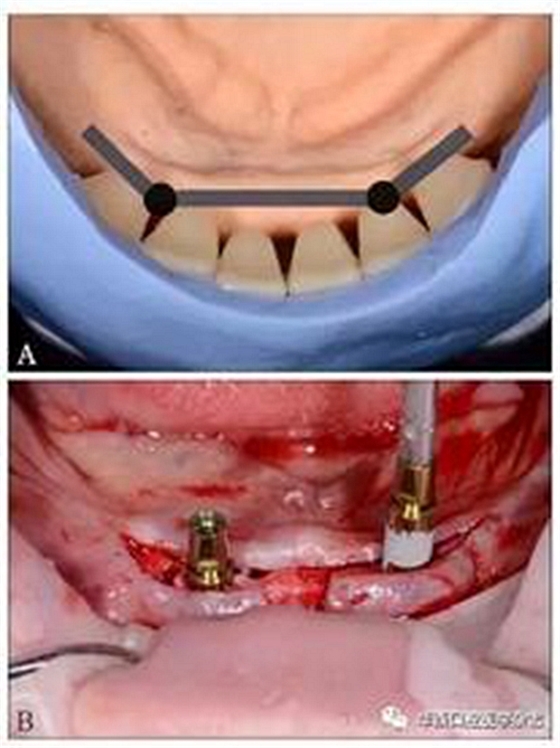

(3)制定治療計(jì)劃:黏膜支持式總義齒修復(fù)上頜無牙頜;種植體-桿卡固位覆蓋義齒修復(fù)下頜無牙頜。根據(jù)人工牙的排列設(shè)計(jì)桿的位置,使桿位于牙槽嵴與人工牙間,并設(shè)計(jì)種植位點(diǎn)(圖3A);運(yùn)用雙側(cè)游離端短懸臂,增加義齒穩(wěn)定與固位[9,13]。依診斷排牙翻制種植手術(shù)導(dǎo)板。

(4)種植手術(shù):依據(jù)種植手術(shù)導(dǎo)板,在下頜雙側(cè)側(cè)切牙與尖牙之間的位點(diǎn)各植入1枚3.8 mm×11 mm種植體(XIVE,F(xiàn)riadent公司,德國),植入扭矩25 N·cm(圖3B)。